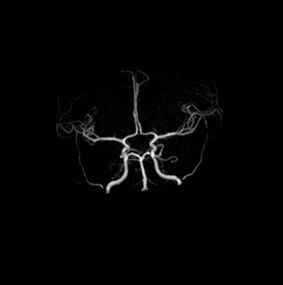

An Occipital Headache as the First Presentation of Multiple Third, Fourth, and Lateral Ventricular Cavernous Malformations: A Case Report and Review of Literature

Background: Cavernous hemangiomas are common benign vascular malformations. Their existence in the intraventricular region is very rare. Case Reports: A 43-year old woman with an occipital headache was admitted to the emergency ward. Brain computed tomography scan showed mild hydrocephalus and multiple intraventricular isodense lesions. Imaging findings, especially of Gradient Resonance Echo imaging, were in favor of multiple intraventricular cavernous malformations. Conclusion: This is a rare presentation of multiple cavernous malformation as occipital headache without needing surgical intervention in this phase. Coexistence of periventricular plaques like Radiologically isolated syndrome of Multiple sclerosis is another unique aspect in this report. [GMJ.2017;6(1):61-65]